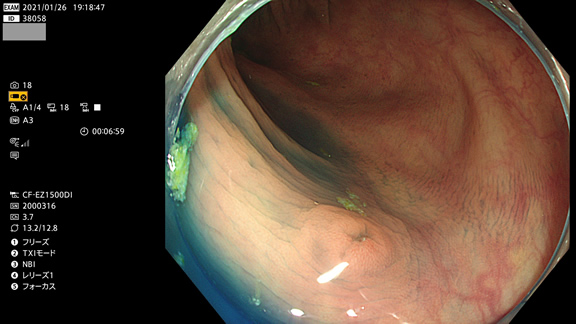

非典型的ポリープの例

これも炎症にしか見えませんが、実は腺腫です(病理で確定ずみ)